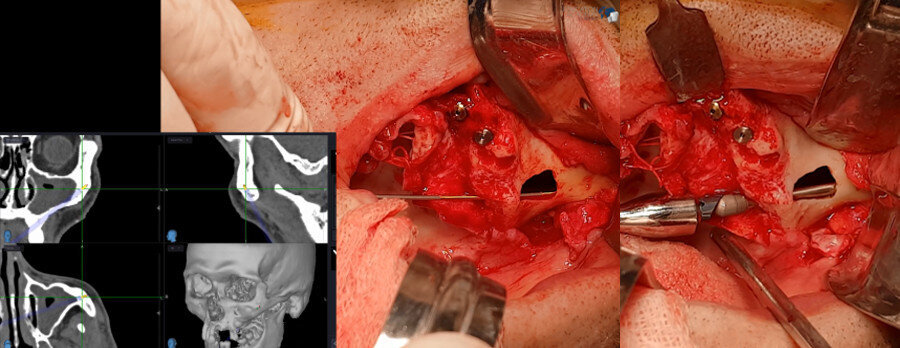

Fig. 8: Intra-op aspect of implant placement.

Fig. 9: Three-D intra-op images provided by the navigation system.

After elevation of a full-thickness flap with bilateral identification of the infraorbital nerves, an osteotomy was performed to create a bone window to access the interior of the maxillary sinus. The navigation instrument most suitable for this type of surgery was chosen for its flexibility, thickness and length (Fig. 5). The images displayed on the monitor are in real time intra-operatively, allowing the alteration and verification of the osteotomy in the space planes. Confirmation of existing bone availability, maintenance of the integrity of the relevant anatomical structures and placement of the zygomatic implant in the ideal position for each clinical case are ensured. Zygomatic implants are placed according to this checklist (Figs. 6a–7b). The 3D positioning of the zygomatic implants allowed excellent primary stability as well as adequate positioning for prosthetic restoration (Fig. 8).

The images provided intra-operatively and in real time are of great definition and highly informative. The system also allows the introduction of a colour code to establish safety limits with respect to the length and diameter of the zygomatic implants. Navigation can also be used for other conventional implants (Fig. 9). After completion of the surgery, a new high-definition CT scan was performed to check the final positions of the two zygomatic implants placed in the posterior of the maxilla and the four conventional implants placed in the anterior sector of the maxilla (Fig. 10).